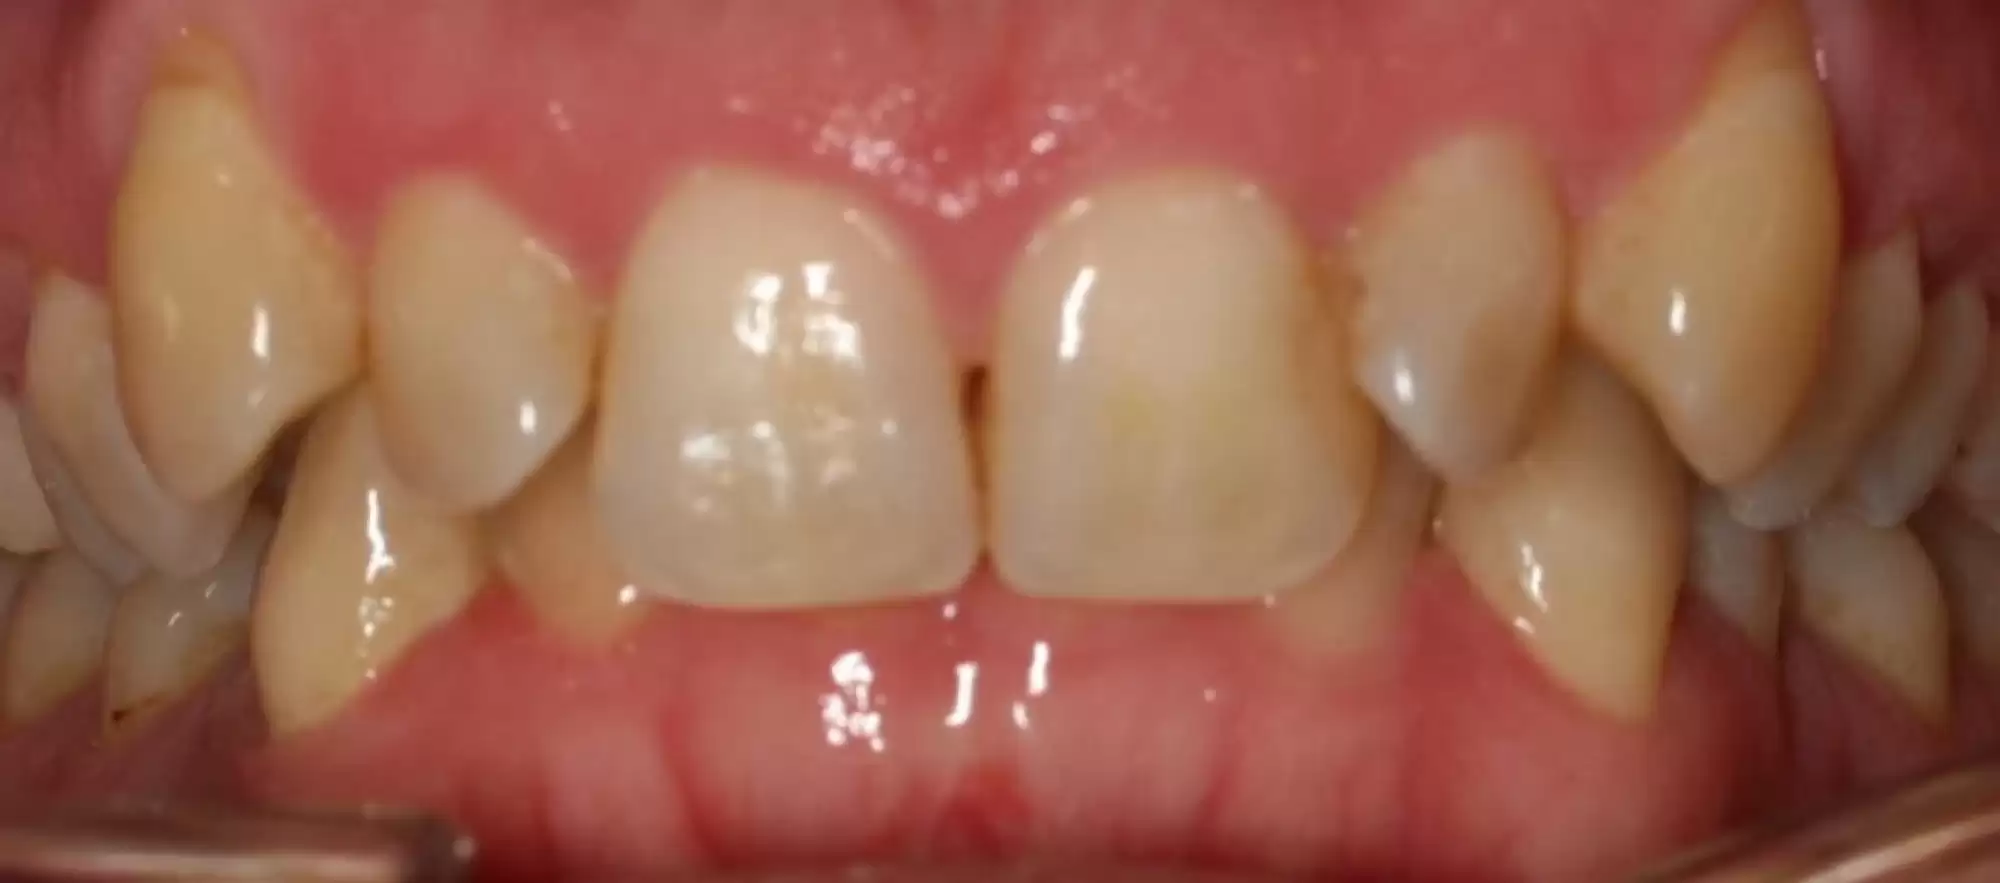

This patient’s spacing problem in the upper jaw was treated with Invisalign.